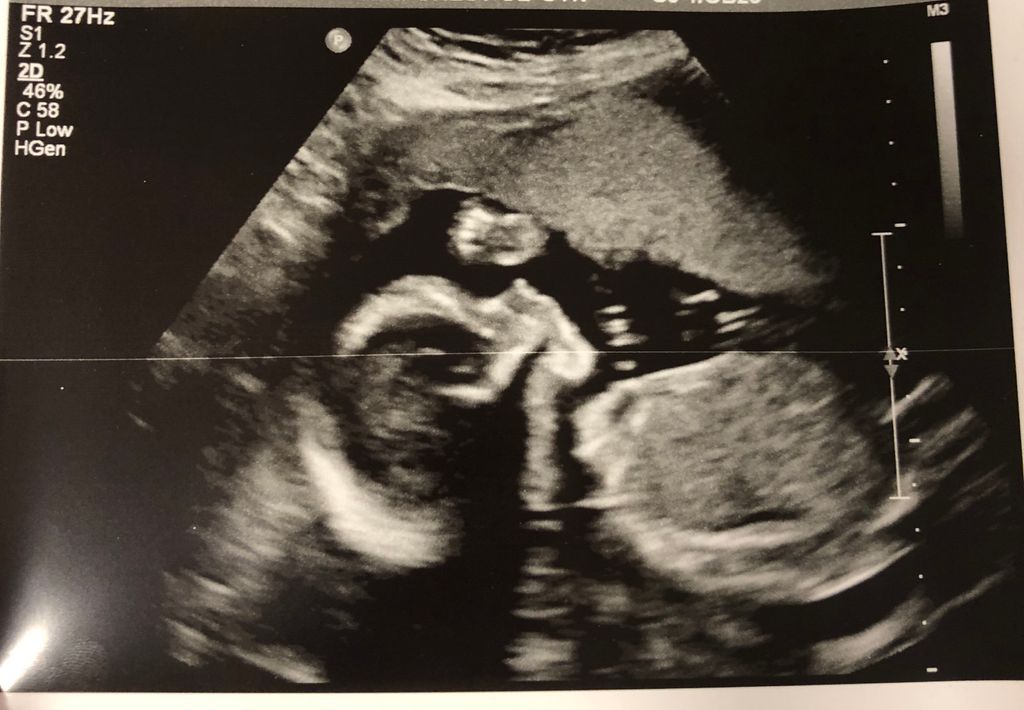

Pregnant Anatomy Scan

The anatomy scan is a level 2 ultrasound, which is typically performed on pregnant women between 18 and 22 weeks. It is a type of ultrasound scan. The scan is performed transabdominally. Learn some early signs that you might be pregnant. A fetal anatomy scan can tell how your baby is developing in your womb.

A detailed anatomy ultrasound is recommended during pregnancy, between 18 and 22 weeks gestation.1 sometimes known as an anatomy scan, . It will tell you if your baby has a health problem . The scan is performed transabdominally. It is a type of ultrasound scan. The anatomy scan is a level 2 ultrasound, which is typically performed on pregnant women between 18 and 22 weeks. Learn some early signs that you might be pregnant. This is a routine screening examination, which should be offered to all women. This is a detailed scan of your baby/babies anatomy. The person carrying out the scan (sonographer) will . Learn how to scan a document to your computer. In women at high risk for preterm delivery (multiple . A fetal anatomy scan can tell how your baby is developing in your womb.